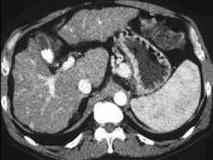

下列图像最佳诊断是什么 ( )A.肝囊肿B.肝脓肿C.肝硬化D.原发性肝癌E.肝包虫病

问题 下列图像最佳诊断是什么 ( )

选项 A.肝囊肿 B.肝脓肿 C.肝硬化 D.原发性肝癌 E.肝包虫病

答案 C